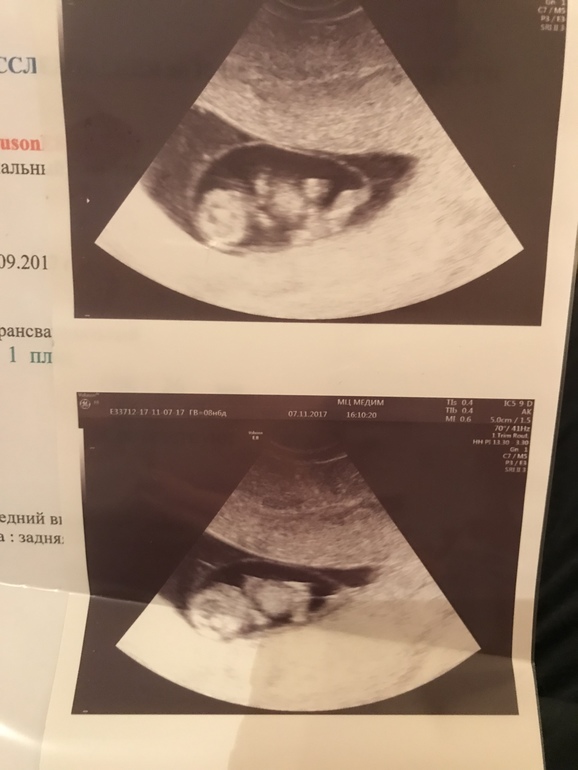

Результаты: УЗИ, КТГ, доплера, скринингаСходила я сегодня на УЗИ (врач говорила пойти в 9-10, и если все хорошо, вставать на учёт). Такой уже малыш 😍 ручки и ножки уже в зачатках, он ими так барахтал 🙈 ой, девочки, весь вечер отойти не могу)) я бы каждый день ходила бы смотреть на него, будь моя воля )))

ну не знаю, по таблицам, которые смотрела я, ктр 23 мм -это 9 недель)) и у нее аппарат выдал срок 9 недель))

Я тож сегодня на УЗИ была 🙈 Не планировала но все признаки б вообще пропали и нервничаю много решила проверить, все ттт мы уже 26.4 😱 Такие большие! Срок 9.3 а яичко у вас какого диаметра? У нас 44 )

41 мм)) а по месячным у вас какой срок? Есть разница с эмбриолетальным?)

Класс,какое четкое узи! Вагинально делали,да? У меня чё то не понятное по животу было на сроке 10 недель

Да, делали вагинально) сверху посмотреть кишечник не дал)) но и аппарат очень хороший)